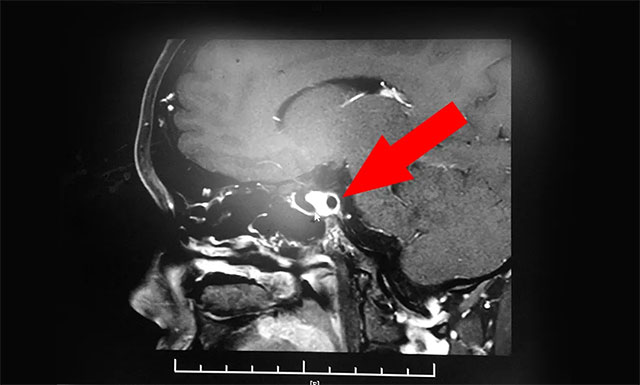

▲ 患者確診為蝶竇囊腫

潘仁龍主任根據(jù)小萌當(dāng)時(shí)所述病癥,并結(jié)合其病史及鑒別診斷,判斷其顱內(nèi)鞍區(qū)可能存在器質(zhì)性病變,隨即對患者進(jìn)行了鞍區(qū)MRI平掃+增強(qiáng),結(jié)果顯示患者腺垂體和神經(jīng)垂體形態(tài)如常,腺內(nèi)未見占位性病變,但在蝶竇部發(fā)現(xiàn)蝶竇性囊樣灶、囊壁和分隔富血供,最終診斷為蝶竇囊腫。